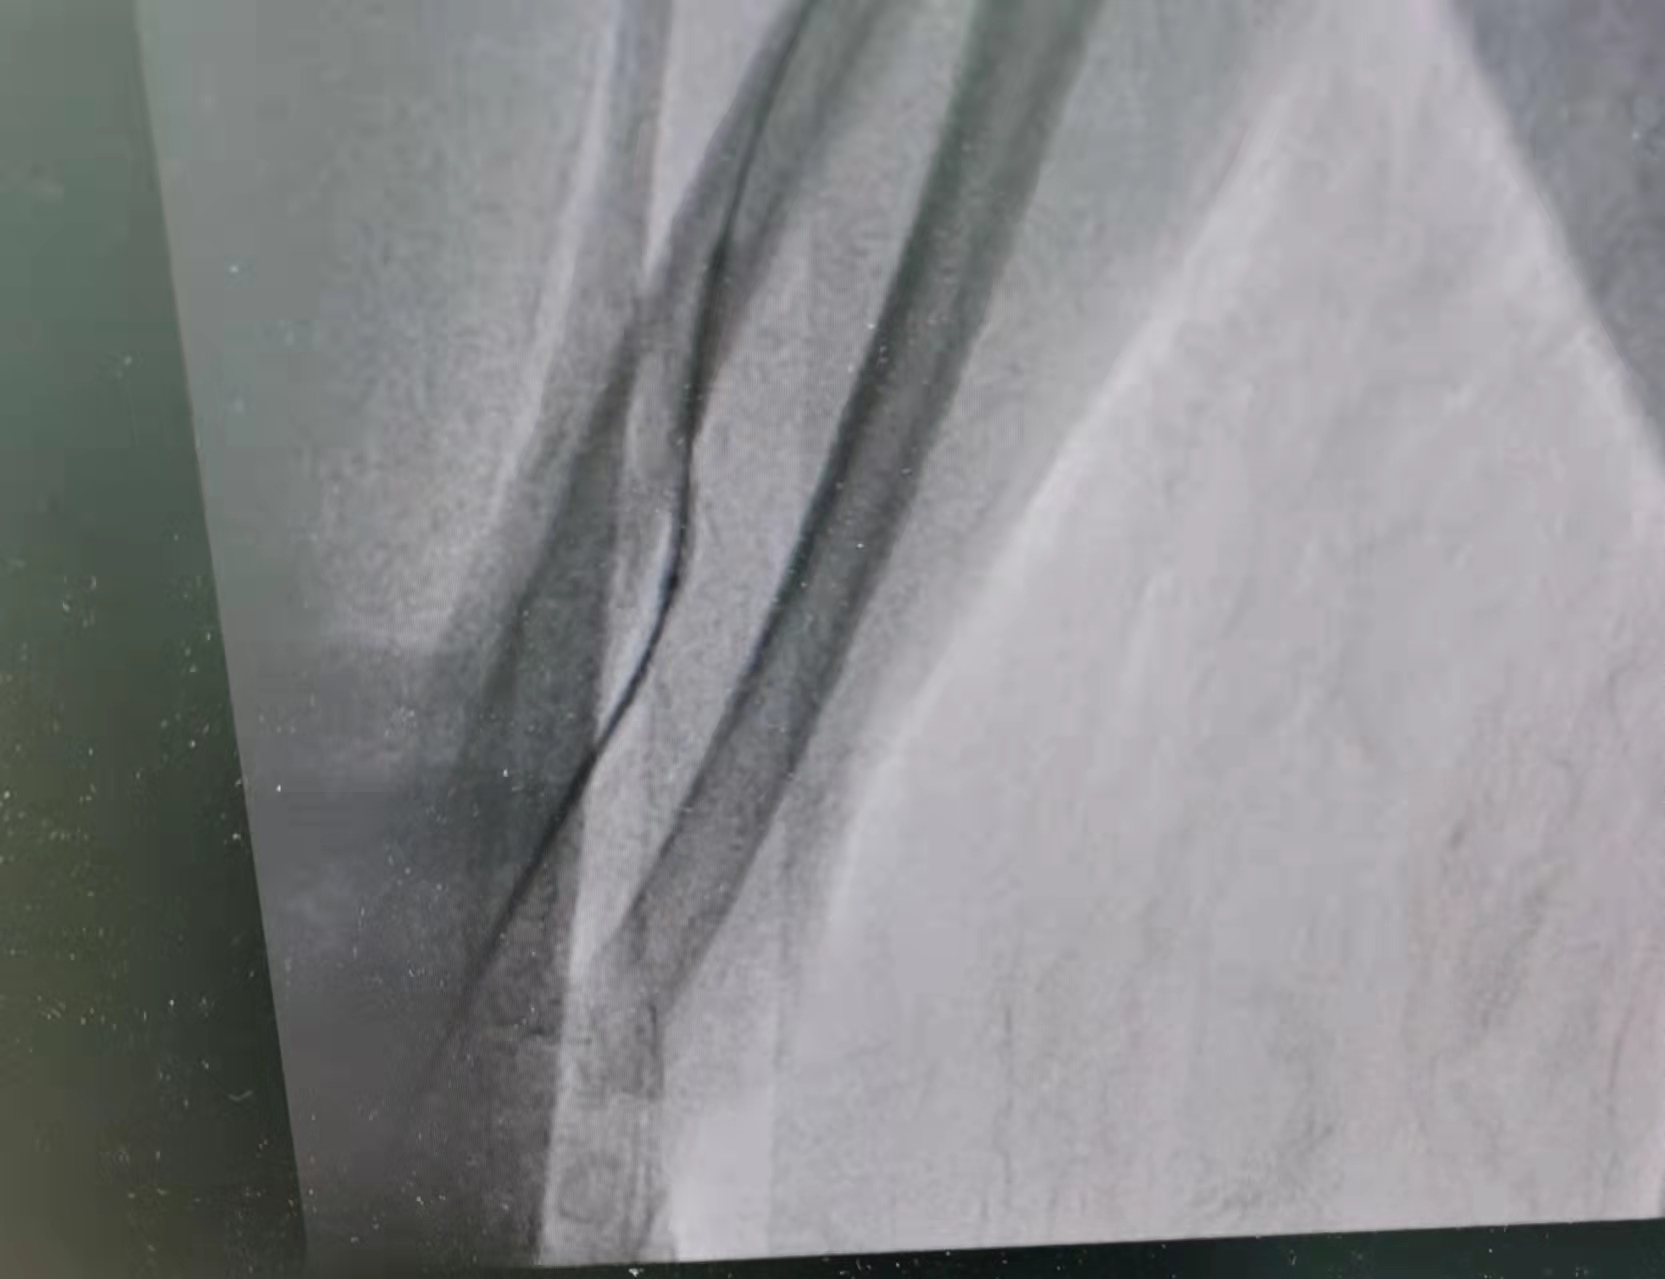

术中,李友河主任及肾内科团队予以在手术部位常规消毒、铺巾、局麻后选择远端桡动脉为穿刺入口,在彩色B超指引下穿刺成功后,按导入血管鞘,血管鞘导入泥鳅导丝,在彩色B超和x线曝光下导丝过内瘘口至头静脉直至贵要静脉近心端再 至上腔静脉,但未入右心房,于以肝素2000U血管注入,影显示内瘘口近心端3cm处头静脉段 重度狭窄, 长约1.2cm;手术过程顺利,术后宗叔血液透析流量良好,可达250ml/min,顺利完成血液透析。目前宗叔已康复出院且内瘘功能良好。

近心端狭窄扩张

近内瘘口狭窄扩张